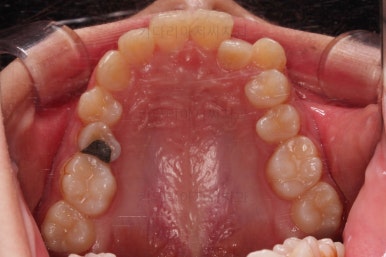

부산교정치료 초진 시 입안의 모습입니다.

치아가 전반적으로 삐뚤고, 덧니가 두드러져 보이네요.

그리고 선을 그려놨는데 윗니의 라인과 아랫니의 라인이 평행이 아니죠.

기울어 있어서 양측의 교합의 강도가 다른 상황이었습니다.